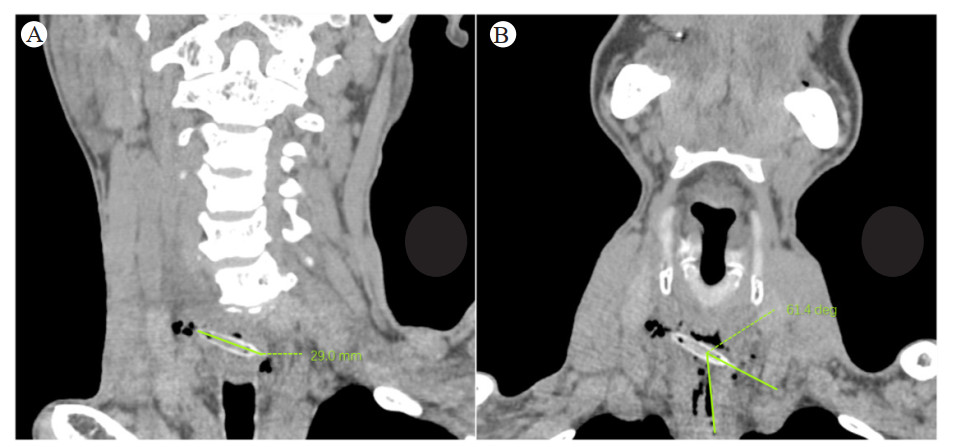

1.3 影像的处理与测量将所得薄层CT影像传送至PHILIPS IntelliSpace Portal工作站进行后处理,利用多平面重组(multiplanar reformation, MPR)技术充分显示食管内枣核全貌及其与食管壁的关系。枣核长度的测量:旋转角度使断层面能恰好展示枣核的最大长轴,测量枣核首尾尖端之间的距离,如图 1A所示;枣核长轴与食管壁夹角的测量:旋转角度使断层面能恰好展示枣核长轴与邻近食管壁,测量长轴与食管壁切线的夹角,如图 1B所示。以上数据均由3名高年资影像医师测量,将所得结果的平均值进行统计分析。

| A:对枣核长度的测量;B:对枣核长轴与食道壁夹角的测量 图 1 食管枣核异物患者影像的测量 |